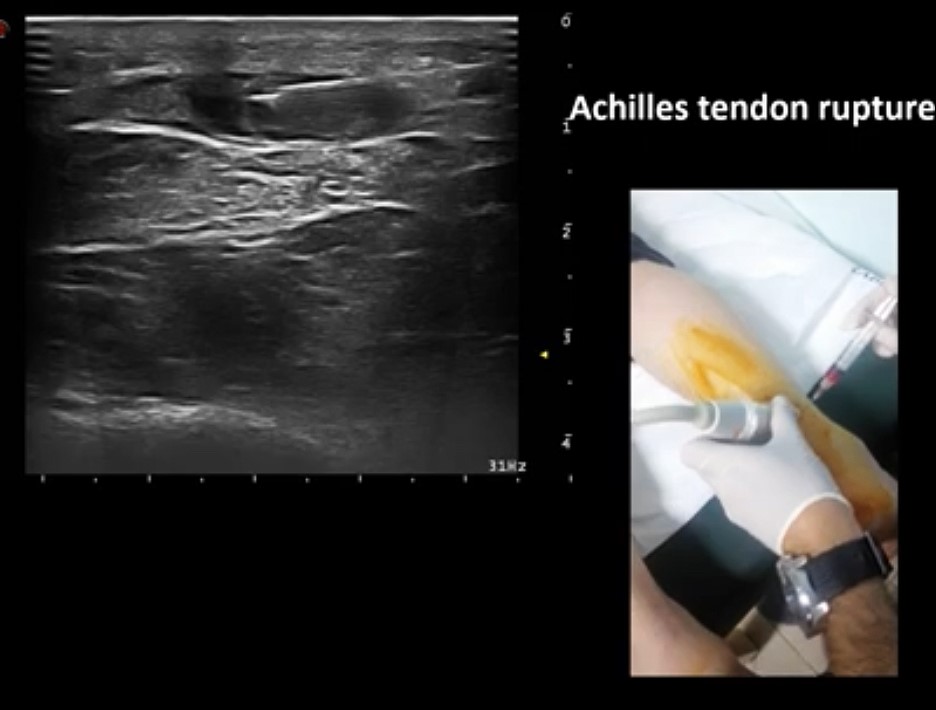

アキレス腱断裂

ギプス固定による保存的治療の治療期間を短縮と治癒率↑を計るために超音波ガイド下に断裂部にPRPを注入します